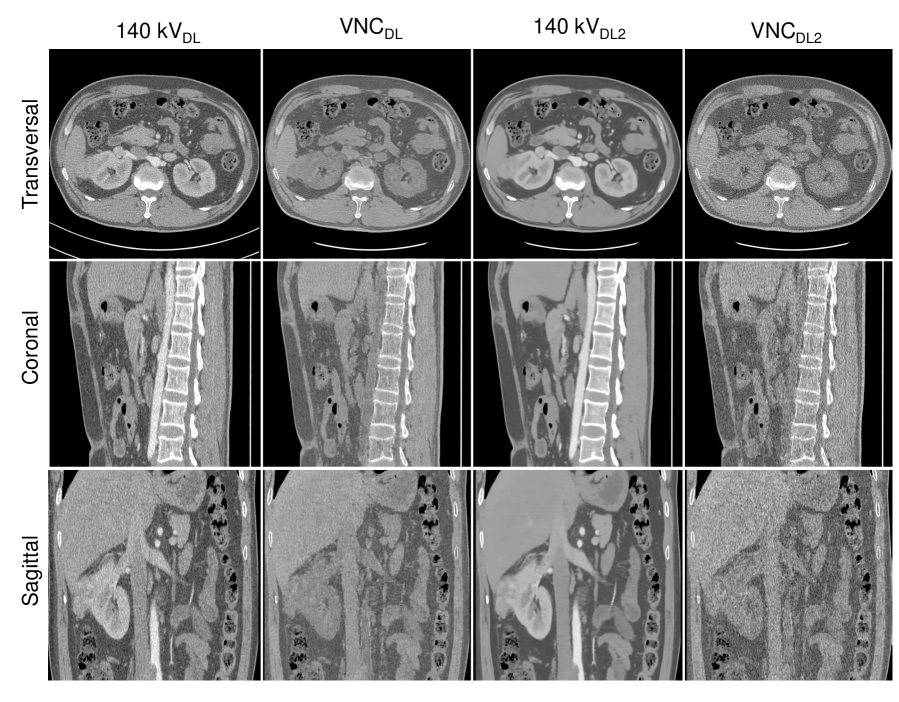

Figure 11: Comparison of material decomposition using DL-predicted 140 kV images in two different options. The 140 kVDL images are obtained by adding the DL-predicted difference images to the raw 100 kV images, and the 140 kVDL2 images are obtained by adding the predicted difference images to the denoised 100 kV images. VNCDL and VNCDL2 are VNC images decomposed using 140 kVDL images and 140 kVDL2 images, respectively. As can be seen, 140 kVDL images preserve noise texture. Although 140 kVDL2 images show significantly reduced noise level, VNCDL2 images show higher noise levels than VNCDL images. All the CT images are displayed with W=500 HU and C=0 HU.

In the proposed predenoising and difference learning approach, the predicted difference image was added to the raw low-energy image (without denoising) to generate the final high-energy image. In order to further show the merit of the approach, we also performed study by adding the difference image to the denoised low-energy image. As shown in Fig. 11, in this case, the final DL predicted 140 kV images (denoted as 140kVDL2140𝑘subscript𝑉𝐷𝐿2140~{}kV_{DL2}) show a lower noise level than the 140 kV images obtained by adding to the raw low-energy images (denoted as 140kVDL140𝑘subscript𝑉𝐷𝐿140~{}kV_{DL}). However, the VNC images decomposed using the 140kVDL2140𝑘subscript𝑉𝐷𝐿2140~{}kV_{DL2} images show a higher noise level than the VNC images decomposed using the 140kVDL140𝑘subscript𝑉𝐷𝐿140~{}kV_{DL} images. This suggests the noises of 140kVDL140𝑘subscript𝑉𝐷𝐿140~{}kV_{DL} images and the low-energy images have been reconciled during material decomposition due to their correlation, showing the merit of the approach.